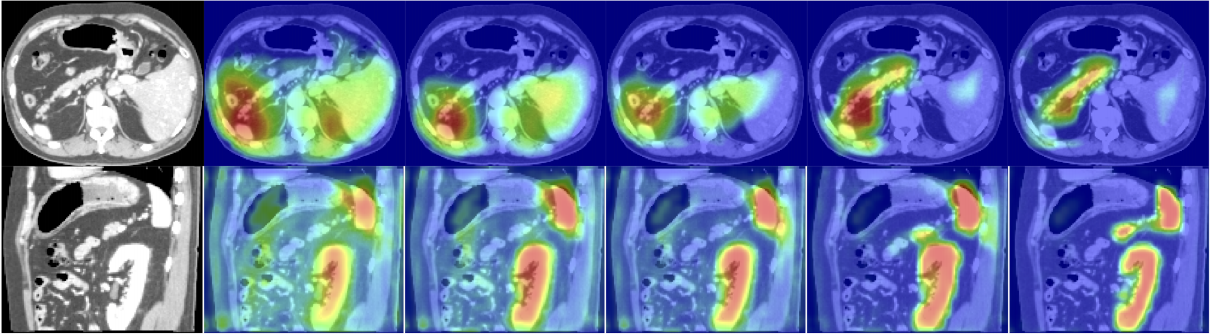

위 그림 5에서 볼 수 있듯 Attention Gate는 학습을 통해서 목적에 맞는 영역에 더 집중하게 된다.